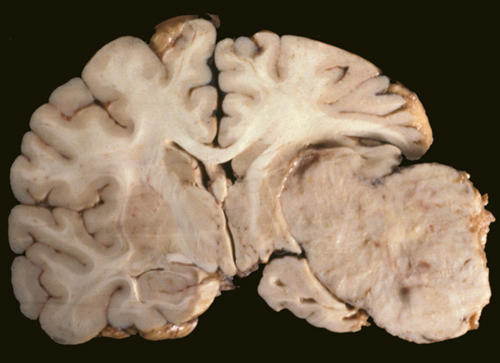

Микрофотографии гистологии глиобластомы головного мозга